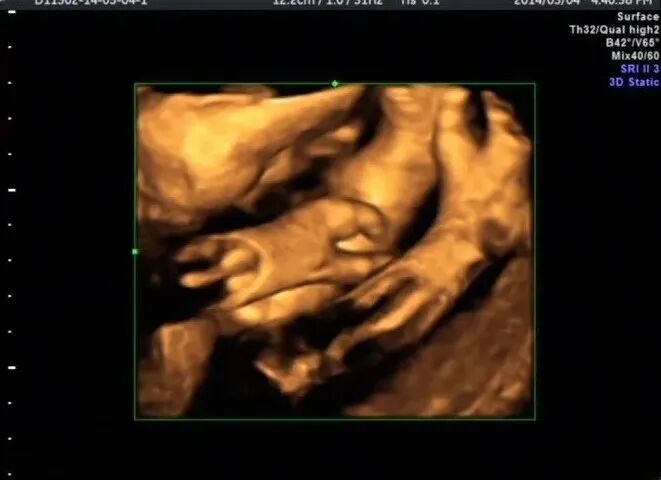

再看脚也不对劲,马上启动三维超声,下图是三维超声表现

手脚都有问题,呈龙虾爪样,非常典型的手裂足裂,胎儿父母没有啥疾病

最后孕妇选择了引产,下图是引产照片

引产结果跟超声图像一样,父母都做了基因检查结果正常。